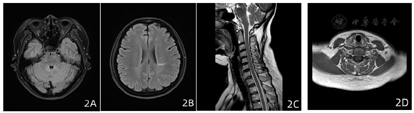

患者发作性右侧肢体无力,激素冲击治疗有效,症状不完全恢复,仍反复发作加重,自加用DMT药物西尼莫德,患者肢体无力症状基本完全缓解,自2021年4月出院后随访至2022年8月,16个月未再复发,末次复查颅脑、颈椎MRI(2021年9月)同2020年7月对比可见脱髓鞘病灶范围明显减小(图2)。现患者无不适主诉,双眼视力1.0,四肢肌力5级,双侧病理征(-),EDSS评分:0分,图3为患者治疗前后EDSS评分比较。